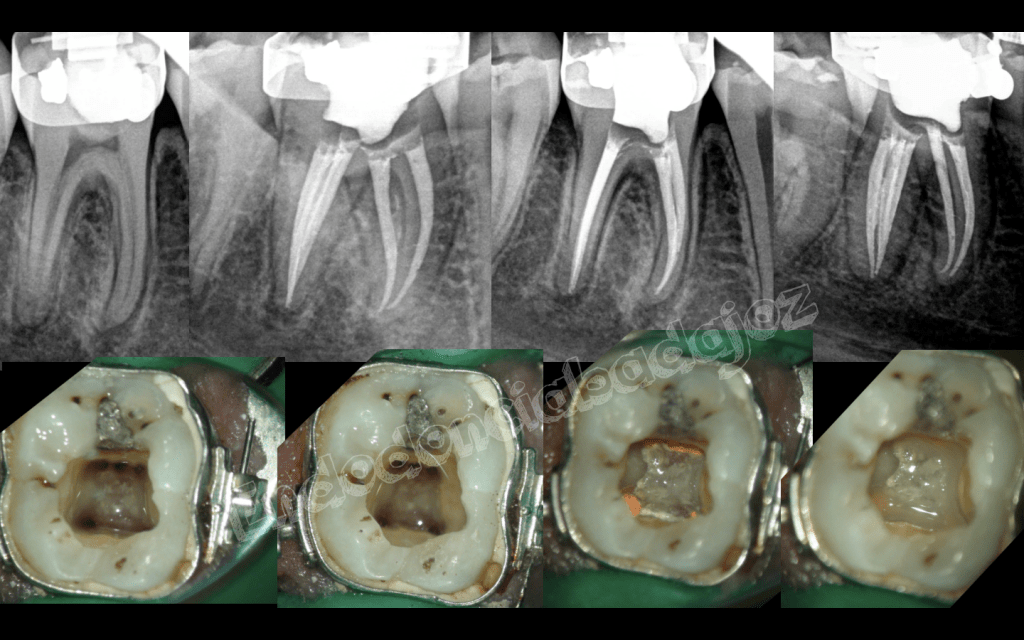

Después de una temporada sin postear ningún caso, hoy me levanté con ganas de publicar alguno, se trata de cinco casos, a mi juicio, interesantes, cuatro endodoncias de molares inferiores con anatomías complicadas y un retratamiento de un molar superior . Espero que os gusten.

Aunque todos los casos son muy buenos, el tercero me parece muy bonito. Podría decirme a qué conducto se unía el MM? El preflaring cómo lo hace usted? Usa Gates o utiliza sistemas rotatorios NiTi?